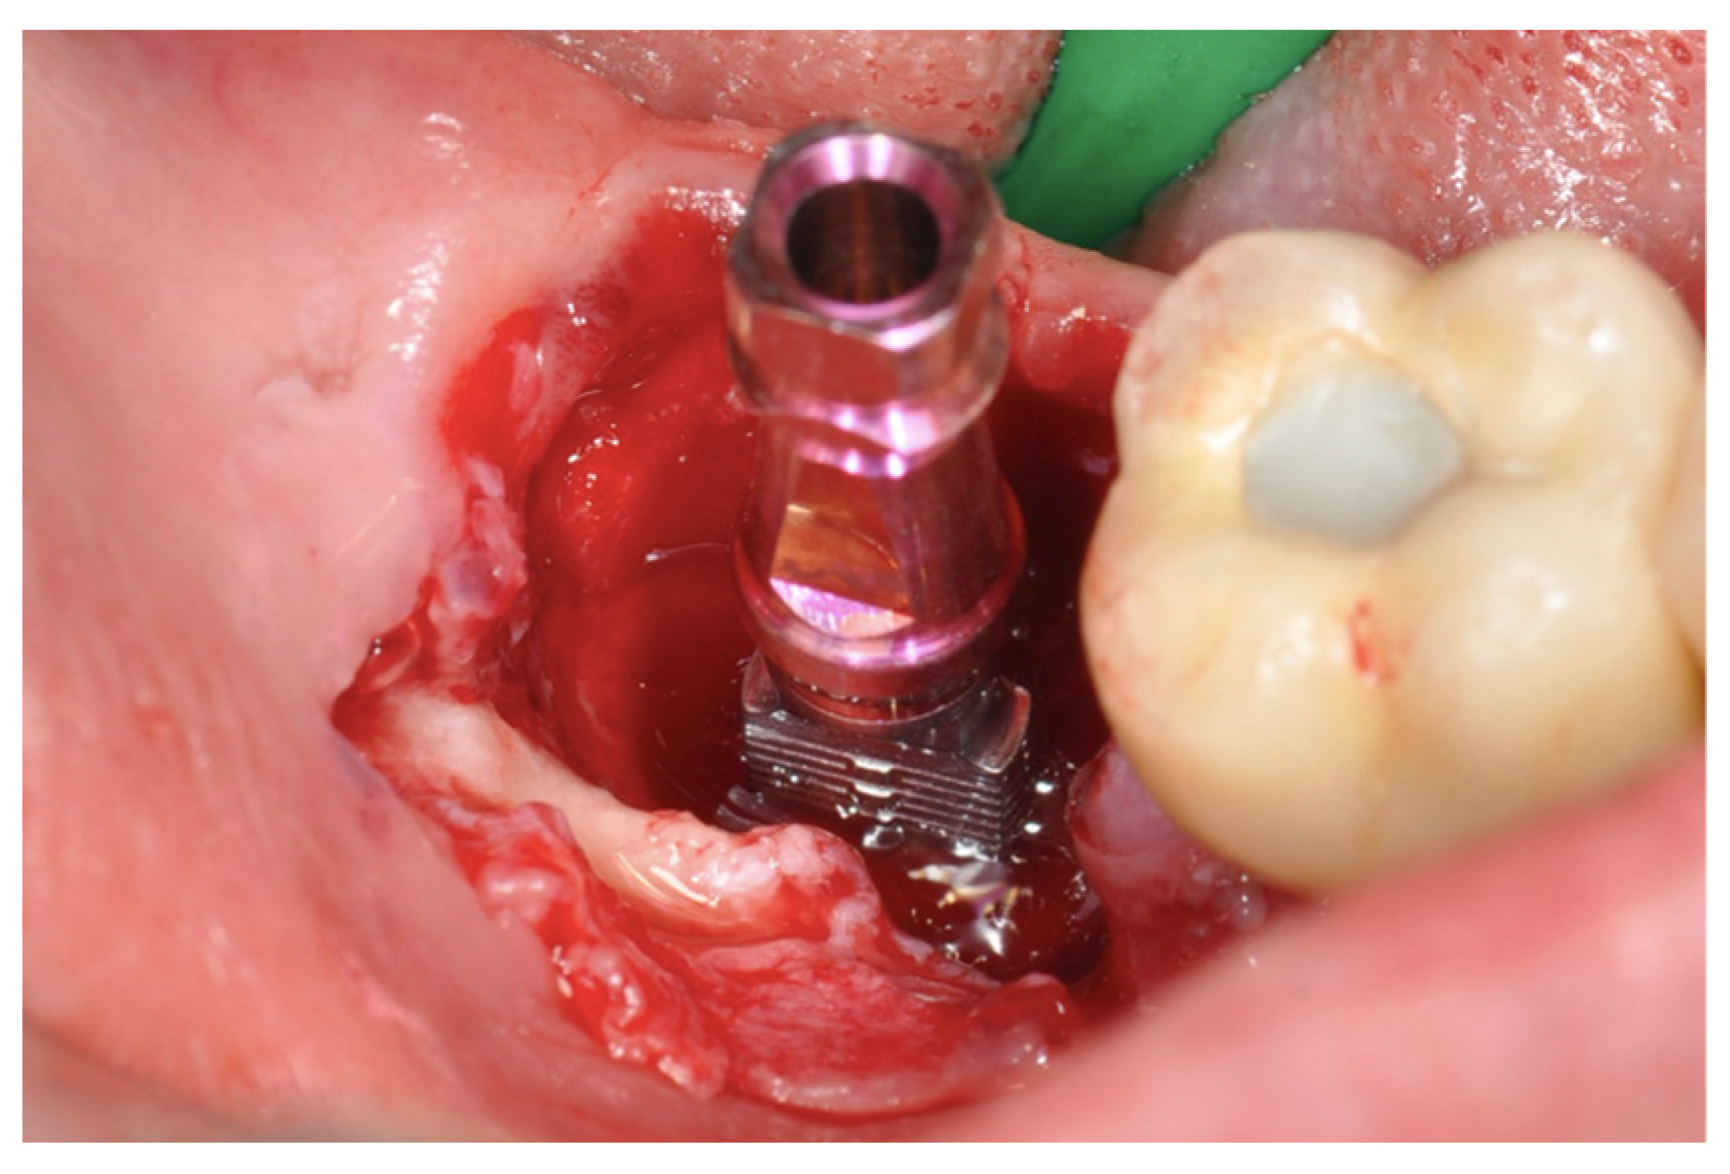

New Operative Protocol for Immediate Post-Extraction Implant in Lower-First-Molar Region with Rex-Blade Implants: A Case Series with 18 Months of Follow-Up

2.2. Surgical Technique